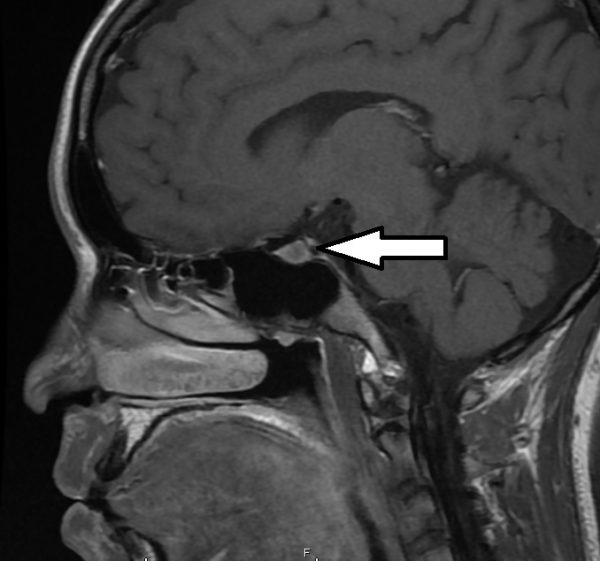

这颗肿瘤体积是2x2x2.5公分,和细小的脑下垂体比较,显得十分巨大,从磁力共振扫描照片上看到,它刚好长在视神经线的交叉处下方,往上推挤视交叉,造成双眼的外侧上端视野丧失。

为了避免视神经线永久性受损,董先生必须接受内窥镜手术,切除大腺瘤。手术时,我请耳鼻专科协助把董先生的鼻窦撬开,让从鼻腔进入鼻窦的手术刀可以深入脑下垂体窝,敲开一个小孔,摘除肿瘤。